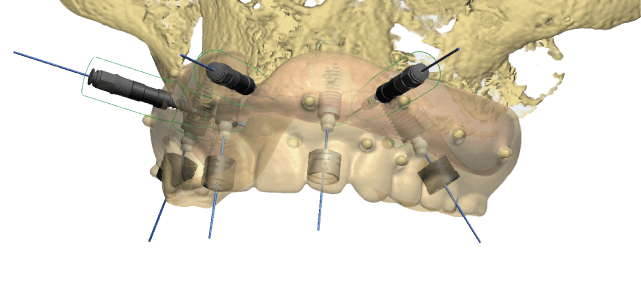

Accept Files from Digital Impression IOS State of Art CT Guided Software

Surgical Guide Surgical Guide Planning

Surgical Guide Planning

-Implant CT Surgical Guide